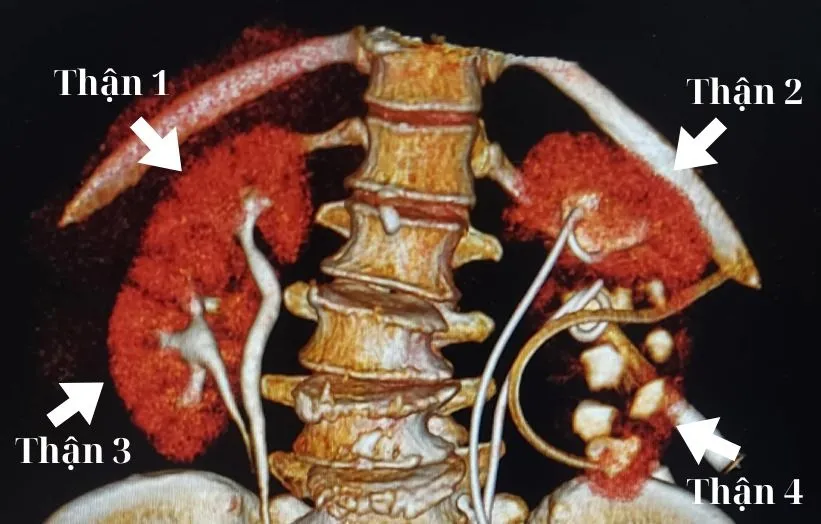

Kết quả chụp chiếu cho thấy bệnh nhân có cấu trúc “thận đôi hoàn toàn” ở cả hai bên, nghĩa là mỗi bên có hai quả thận tách biệt. Ngoài ra, bà bị sỏi niệu quản gây ứ nước ở đơn vị thận dưới bên trái. Tình trạng thêm phức tạp do hẹp niệu quản từ ca mổ trước, khiến việc điều trị gặp nhiều thách thức.

Đây là trường hợp hiếm gặp, đòi hỏi sự can thiệp chính xác để đảm bảo sức khỏe cho bệnh nhân.

TS.BS Nguyễn Đình Liên giải thích dị tật 4 thận xảy ra do mầm niệu quản trong bào thai phân chia bất thường, tạo ra nhiều thận hơn bình thường. Dù nhiều người mang dị tật này không có triệu chứng, một số có nguy cơ nhiễm trùng, sỏi thận hoặc ứ nước.